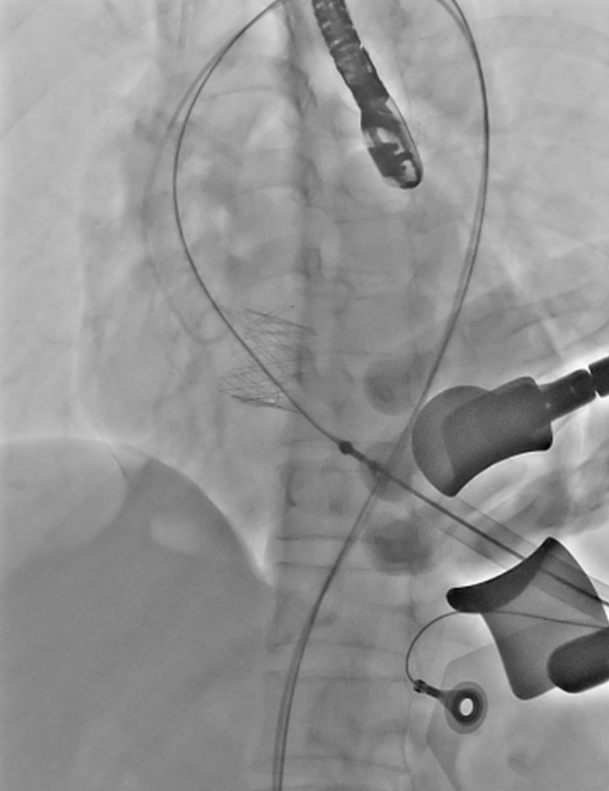

手术当日,在周亚峰教授指导下,心内、胸外等多学科团队充分发挥协作优势。术中凭借经食道超声实时导航,精准定位心尖穿刺点并预缝双层荷包。然后,通过DSA透视引导,将人工瓣膜经心尖输送系统沿导丝轨道推送至病变主动脉瓣区。

团队娴熟操作导丝输送系统,精准调整角度,确保J-Valve人工瓣膜的定位翼准确嵌入主动脉窦部。瓣膜释放后造影显示,人工瓣膜形态位置理想,原有的重度主动脉瓣反流消失。整个关键瓣膜置换步骤仅耗时30分钟,并且患者术后即刻苏醒,未出现传导阻滞、出血等并发症,复查超声证实人工瓣膜功能良好。目前患者已平稳出院,恢复良好。